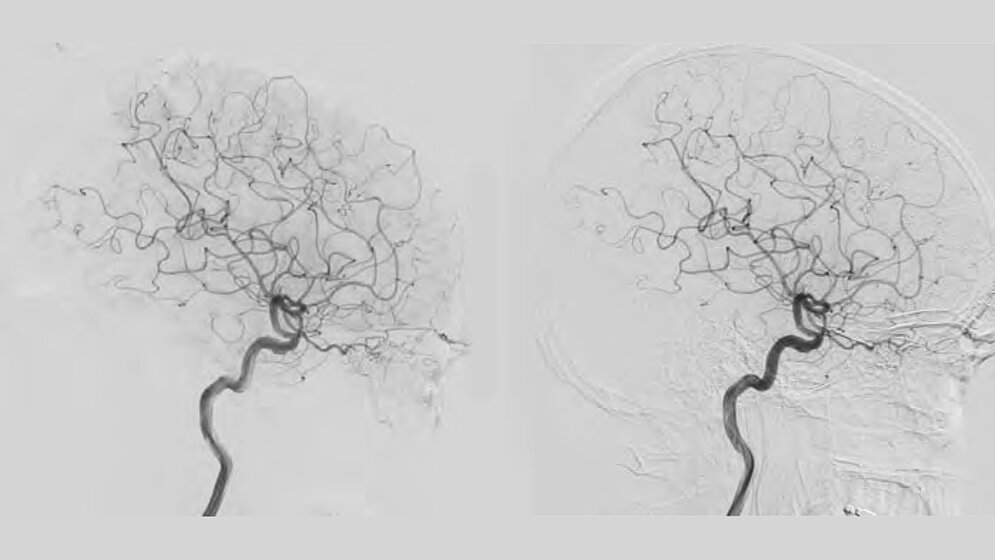

Die steigende Anzahl endovaskulärer Prozeduren, immer adipöser werdende Patientenkollektive, komplexere Prozeduren und kleinere Implantations-Devices sorgen für das Risiko einer höheren Strahlenbelastung für Patient und Anwender in der interventionellen Radiologie. Die Erzeugung von Röntgenstrahlen und ihre schädigende Wirkung auf den menschlichen Körper unterliegen physikalischen Gesetzmäßigkeiten. Eine isolierte Reduktion der Strahlendosis hat immer einen direkten Einfluss auf die Bildqualität am Detektor. Aktuelle Studien belegen nun den Nutzen neuartiger Bildverarbeitungstechnologien wie ClarityIQ zur signifikanten Strahlendosisreduktion, ohne die Bildqualität negativ zu beeinflussen.